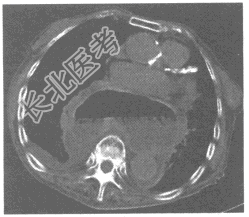

- 单项选择题患者,女, 83岁,胸部CT图像如下。则最确定的诊断为

A、食管裂孔疝

B、胸主动脉瘤

C、胸主动脉夹层破裂

D、后纵隔囊实性占位性病变

E、无明显异常